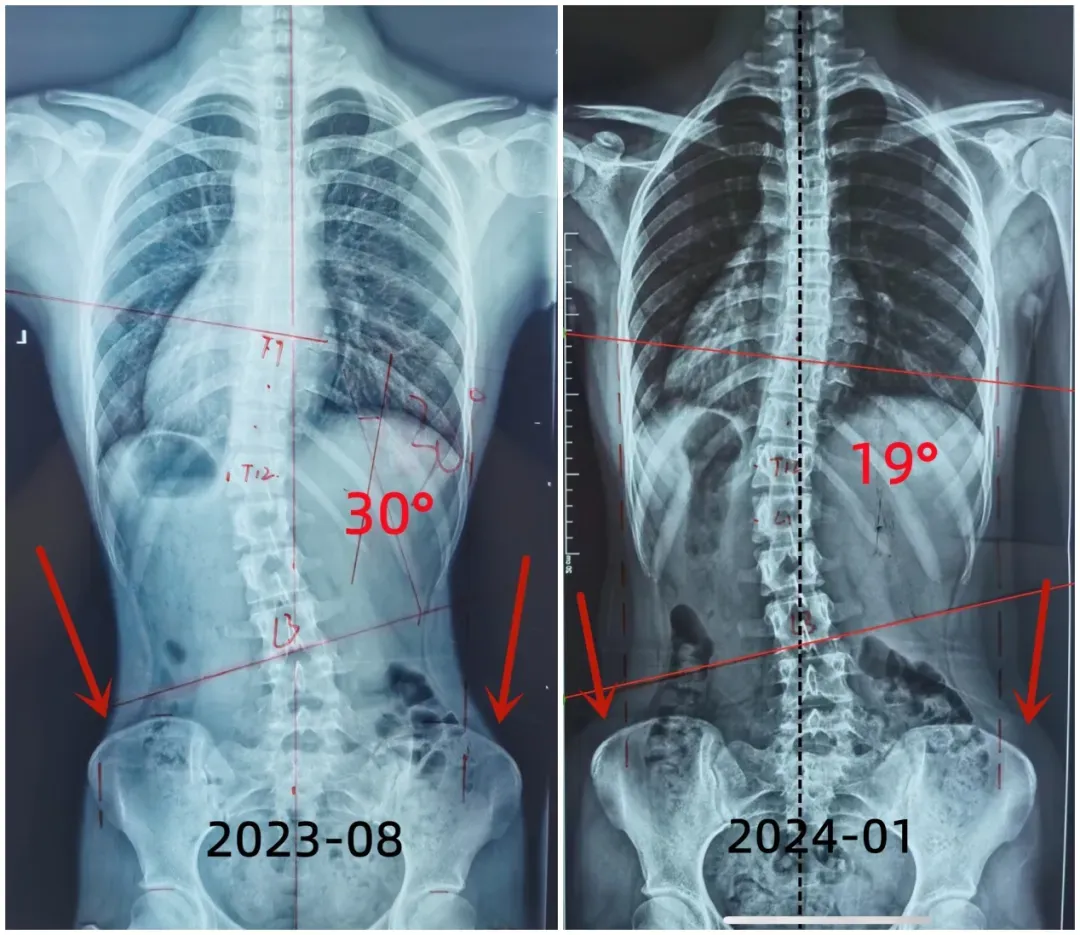

2023年8月经过医生详细的检查和评估,发现小许脊柱侧弯Cobb角度数增长至30°,治疗师为小许设计个性化的施罗斯体操训练。

回家后的小陆每天坚持1小时进行施罗斯训练,让我们看看小许经过五个月治疗后的脊柱情况吧。

我们可以看见,孩子侧弯度数从五个月前的30°减少到现在的19°,降低了11°。身体中线也由原本的向左侧偏移变成了相对居中。右移的臀部也回到了居中的位置。从外观上看,腰椎右侧明显变饱满了,双侧腰线对称了。

小朋友已经16岁,同时从片子中看到骨龄已经接近5级,骨骺线即将闭合,处于青少年生长发育的中后期。这个时期的小朋友更要与时间赛跑,争取早日恢复。小许能够在5个月的时间取得较好的恢复效果,可见施罗斯疗法的临床效果极佳。